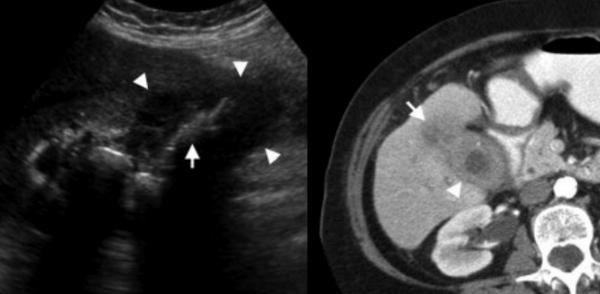

(Левый) При остром холецистите на поперечном УЗ срезе визуализируются смещающиеся книзу под действием гравитации конкременты желчного пузыря и сладж. Обратите внимание на утолщение стенки желчного пузыря и воспаленную эхогенную жировую клетчатку с медиальной стороны.

(Правый) Этот же пациент. Аксиальная КТ с контрастным усилением. Определяются растянутый желчный пузырь с утолщенной стенкой В, смещающиеся книзу под действием гравитации конкременты и сладж. Обратите внимание на исчерченность перипузырной жировой клетчатки.